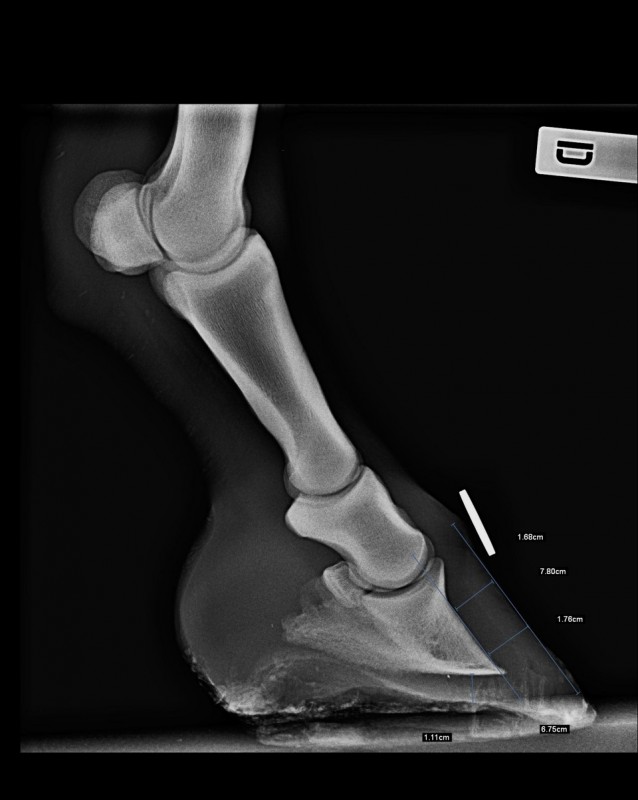

- il a été ferré régulièrement jusqu'à l'hiver de ses 4 ans. Le pied était plutôt bien revenu. J'ai donc décidé de le déférer pensant bien faire. 2 semaines après le déferrage grosse crise de fourbure. La radio de l'antérieur droit montrait un basculement de la 3ème phalange avec une forte décalcification osseuse. Sur les conseil du maréchal et du véto je l'ai laissé tranquille toute l'année suivante (ballade en main et travail en liberté en carrière)

- je viens d'effectuer une radio de contrôle (un an après) et le diagnostic n'est pas rassurant : "la troisième phalange est remaniée mais l'alignement est correct. On note toujours une zone suspecte de déminéralisation sur la vue de face. Nous vous conseillons la ferrure LAMINITIX de M. VAILLANT" (=110€ la ferrure...). Le vétérinaire m'a conseillé d'éviter les sols caillouteux (moi qui rêvais de partir en rando plusieurs jours). Il m'a vaguement parlé des injections de Tildren mais sans trop me rassurer sur leur efficacité. Aucune piste de solution d'un point de vu alimentaire (mon cheval est au foin tout l'année). A noter que maintenant le cheval présente une seime sur l'antérieur droit.

Je vous mets ci dessous les radios de l'antérieur droit ainsi que le visuel du fer conseillé.